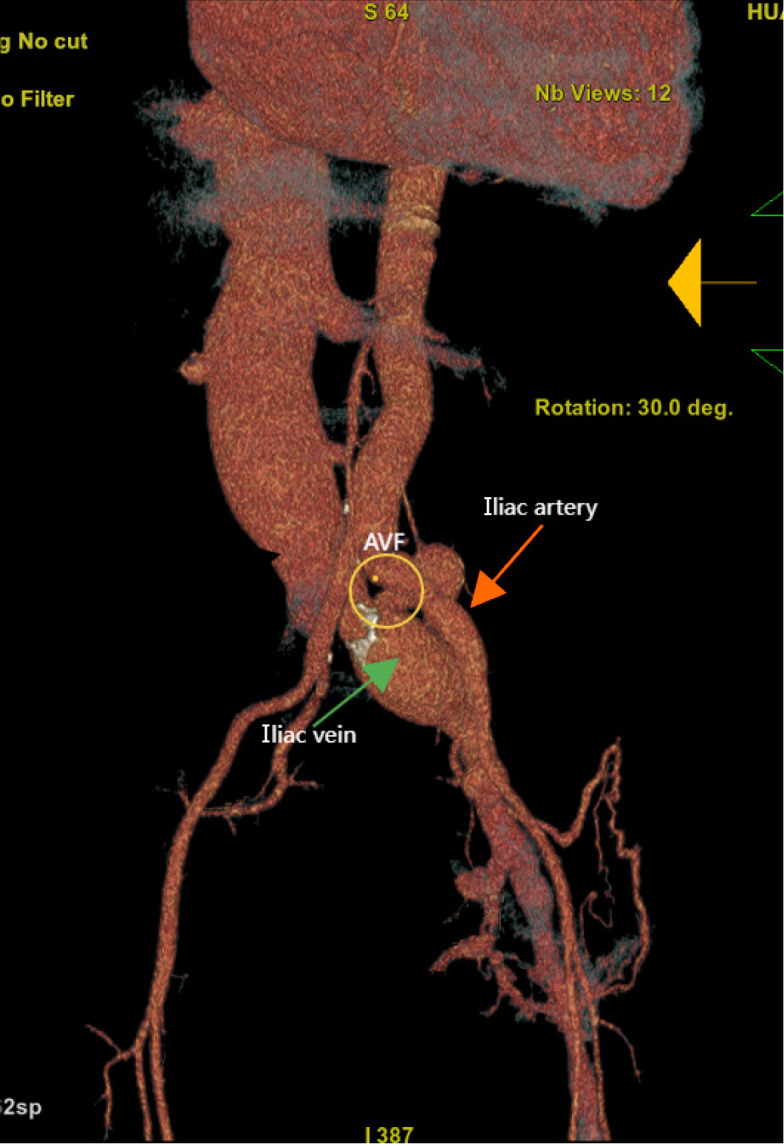

Case summary: A 57-year-old man was admitted to the hospital with complaints of exertional dyspnea for more than 10 years. Physical examination revealed wet crackles in the lungs and a continuous machinery murmur in the left lower back and groin area. Asymmetric edema and varicose veins were observed in the lower limbs. Echocardiography revealed a dilated right ventricle with severe pulmonary hypertension. Computed tomography revealed a left common iliac arteriovenous fistula linked to prior lumbar disc surgery. Surgical repair resolved the symptoms, with echocardiography at 4 months showing a reduced right atrium (RA) and ventricular (RV) diameter and tricuspid regurgitation. However, during the 2-year follow-up, gradual RA and RV re-expansion (from 35 mm to 51 mm and from 26 mm to 46 mm, respectively) was observed, despite sustained clinical stability.